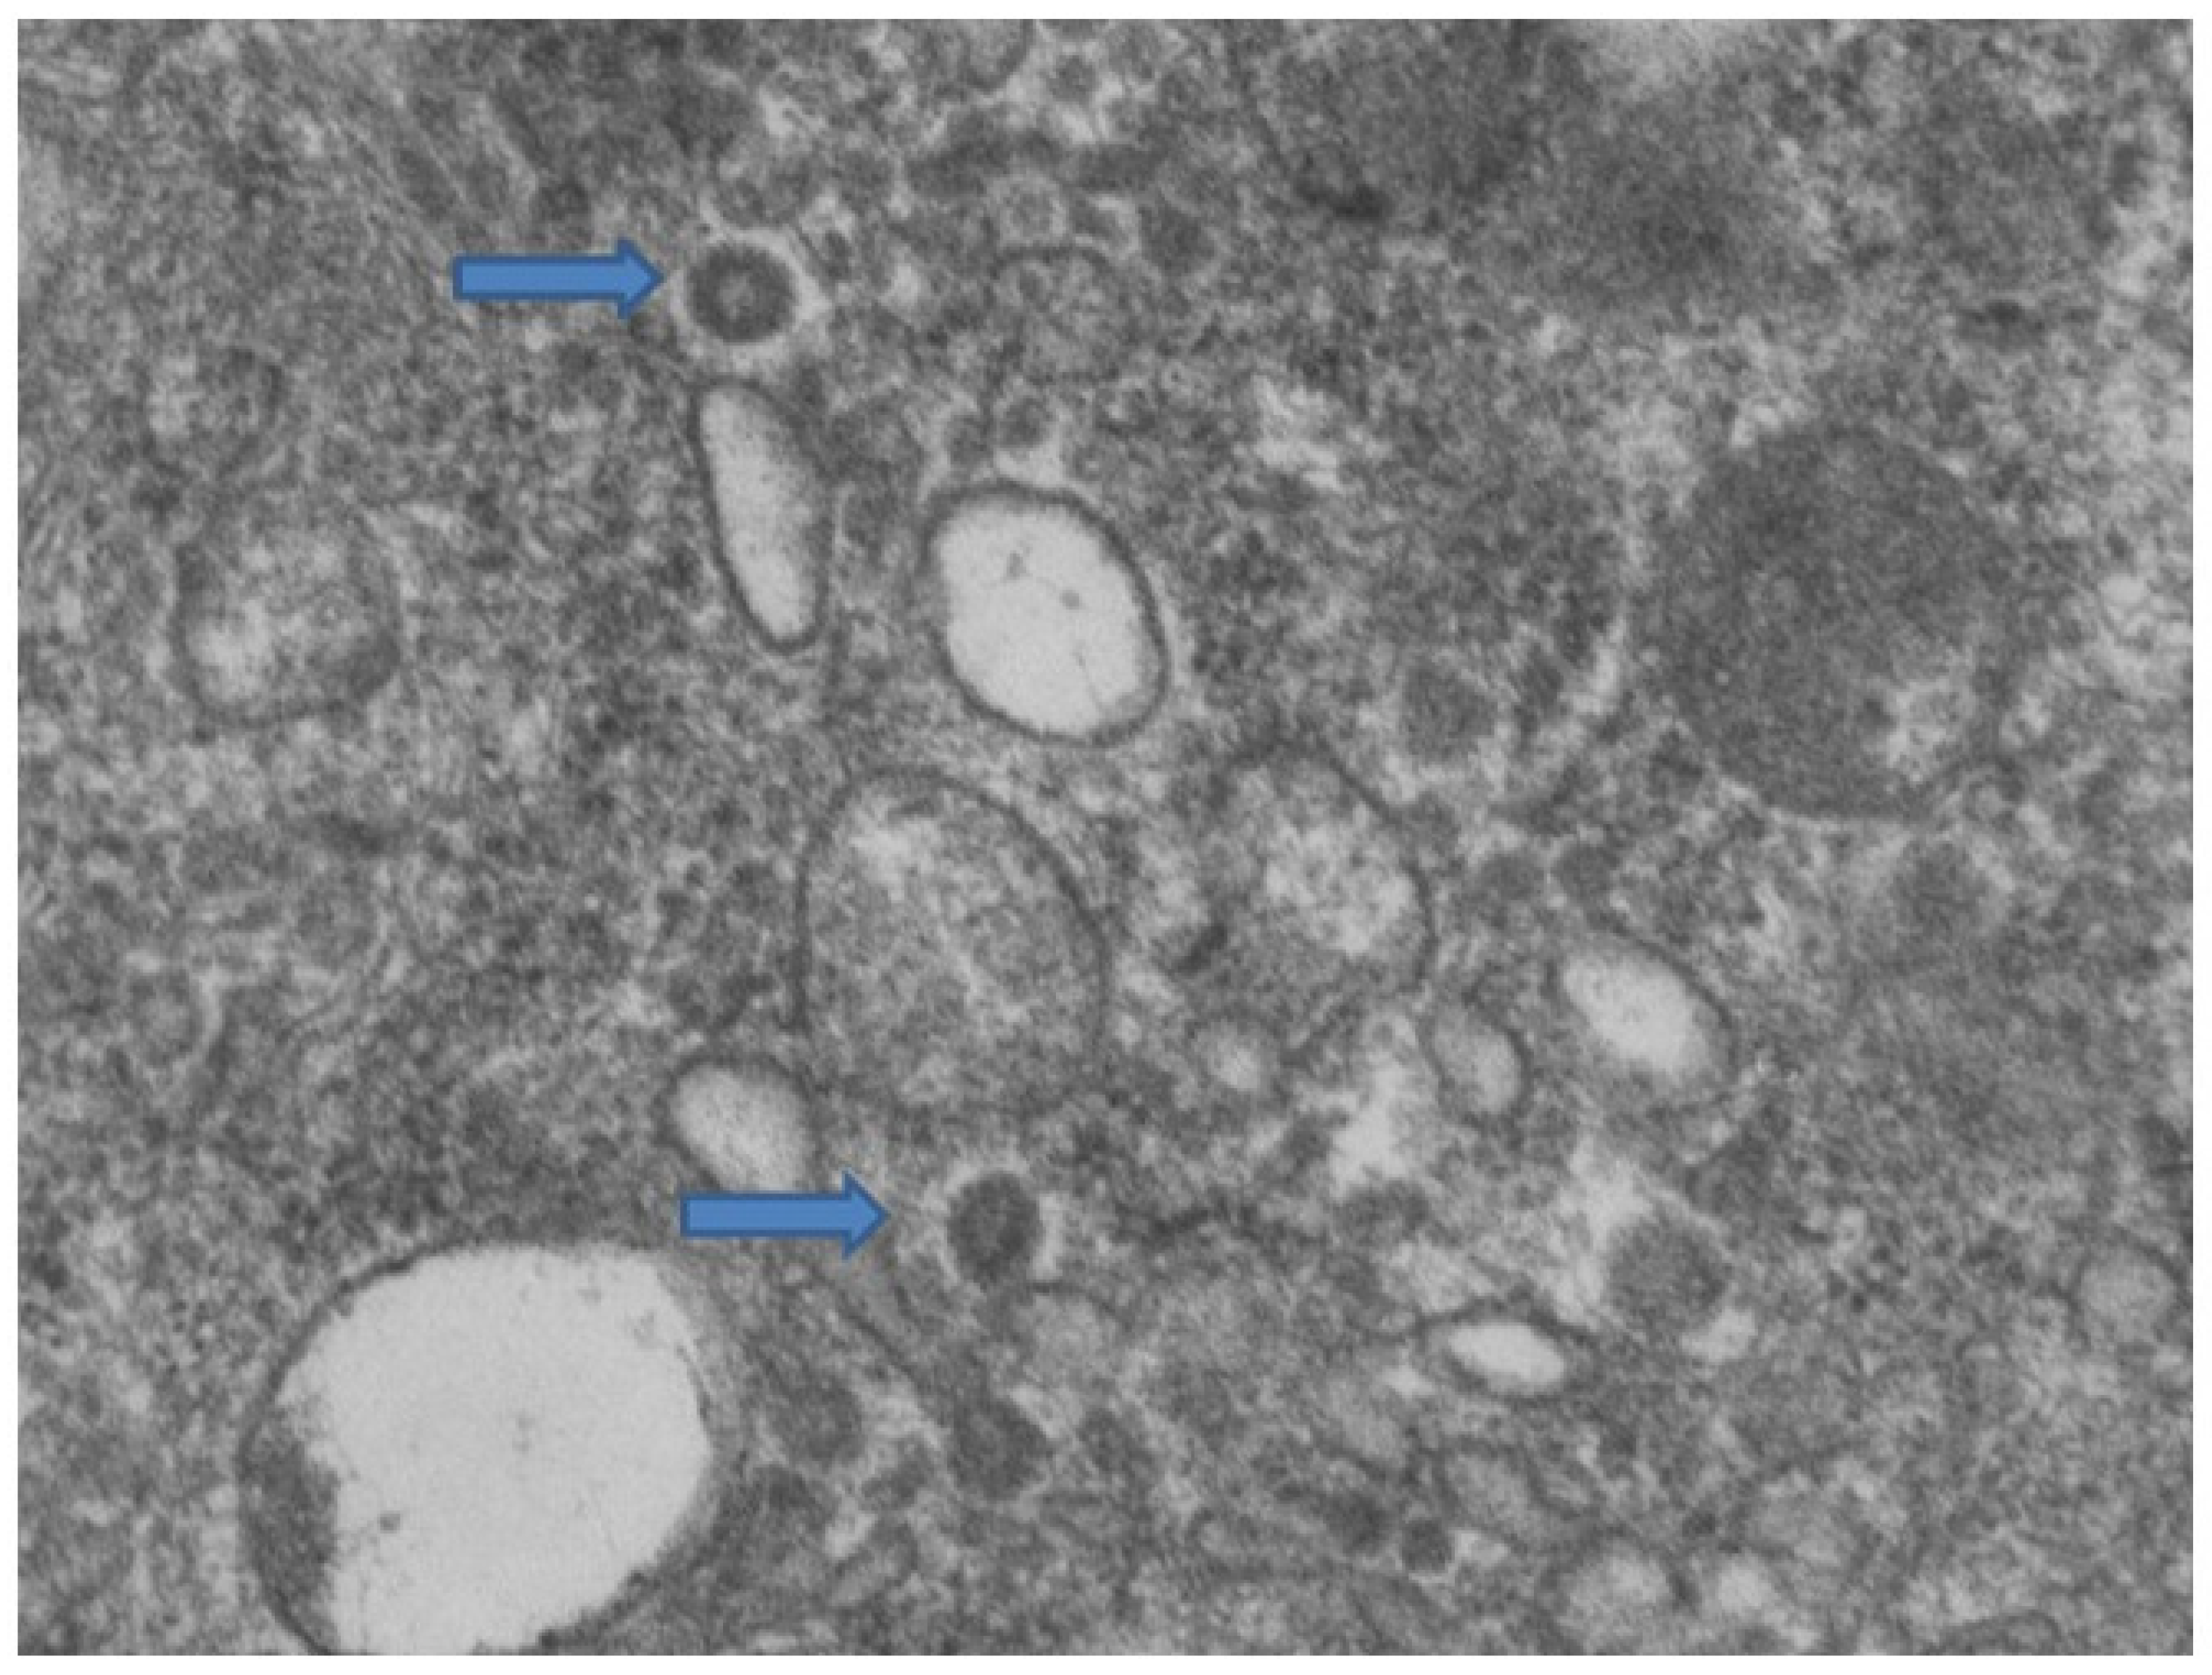

3.1. Erythema-Multiforme Like Eruptions

3.2. Pseudochildblains